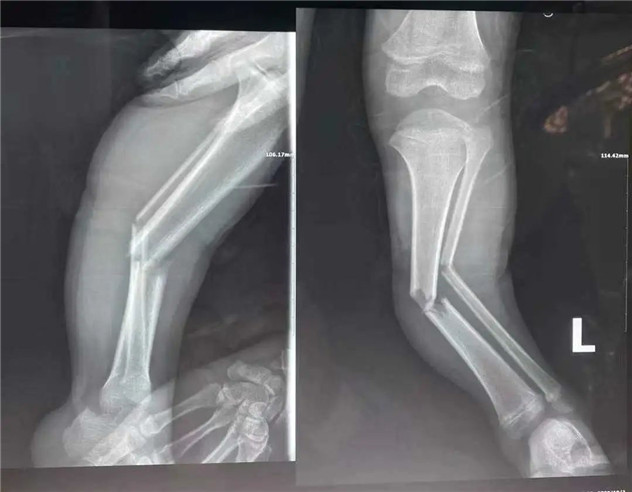

經(jīng)拍片顯示,睿睿左脛腓骨中段粉碎性骨折。接診的我院骨科中心主任羅軍建議其入院接受手術治療。

術前